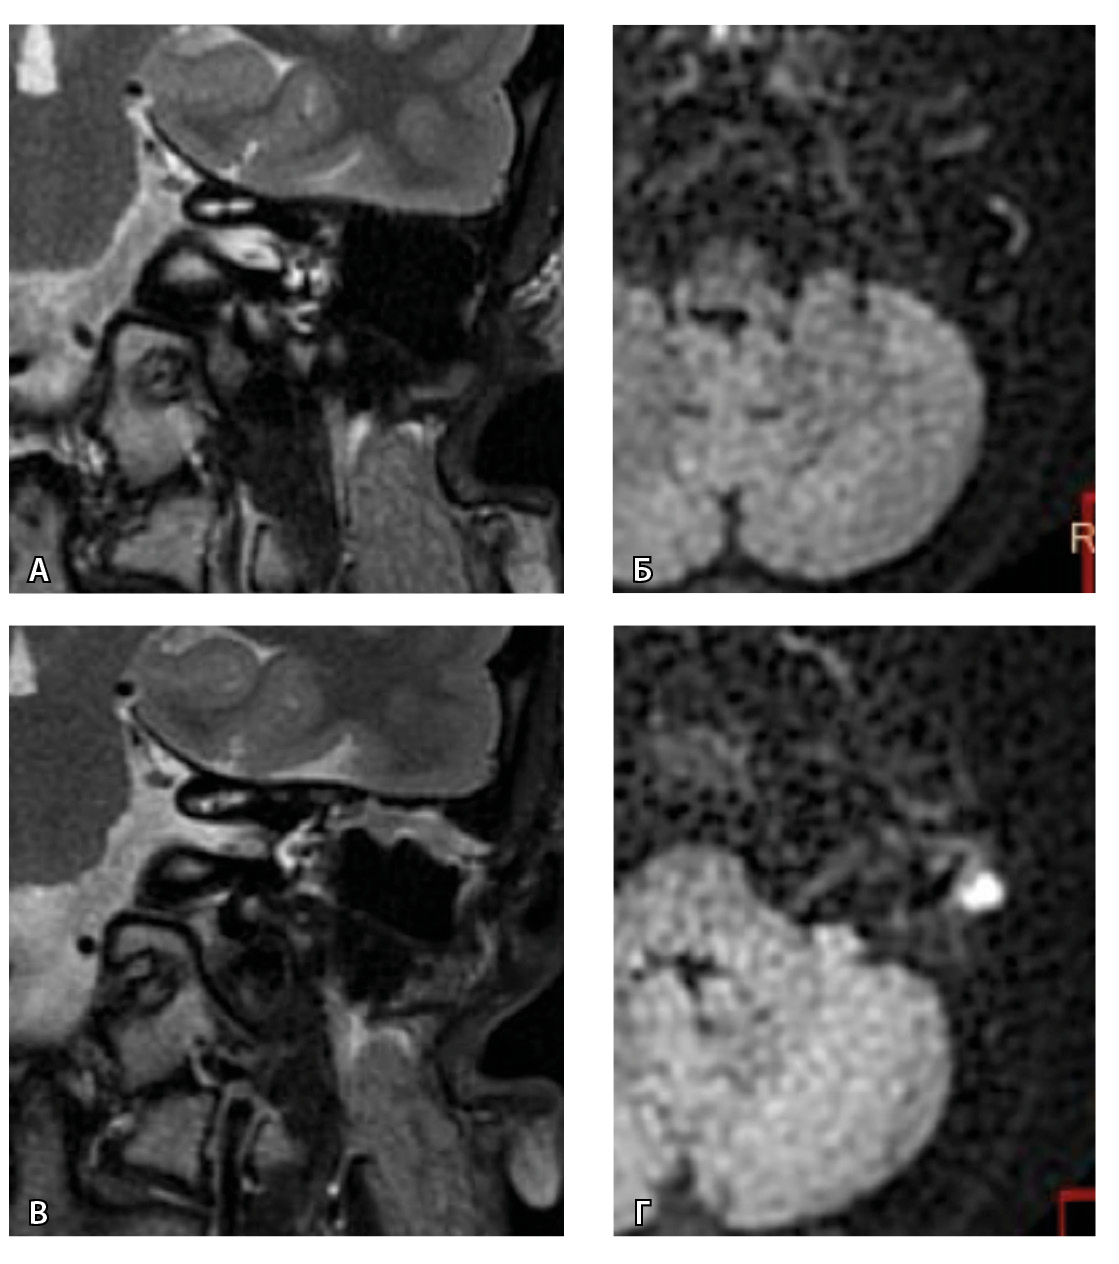

Рис. 5. При первичном послеоперационном исследовании на Т2-взвешенных изображениях во фронтальной плоскости определяется пневматизированная послеоперационная полость (А), без признаков ограничения магнитно-резонансной диффузии (Б). При контрольном исследовании – отрицательная динамика с появлением пристеночных разрастаний вдоль стенок послеоперационной полости (В), ограничивающих магнитно-резонансную диффузию (Г). Данные интерпретированы как рецидив холестеатомы. При оперативном лечении и последующей гистологии – грибковое поражение среднего уха